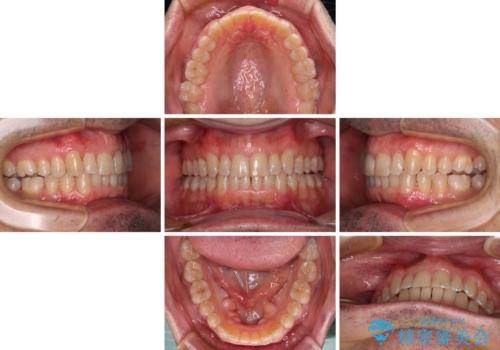

- 前歯のデコボコを気にして来院された患者様です。

インビザラインでもワイヤー装置でも対応可能でしたが、仕事の都合で来院回数を減らしたいとのことでインビザラインによる矯正治療を選択されました。

著しく咬合力が強いため、奥歯がしっかりと噛めずに治療が長引くことが懸念されました。

1セット目のインビザラインを使用した際には左右ともに大臼歯が咬み合っていなかったのですが、2セット目できっちりと仕上げることができました。